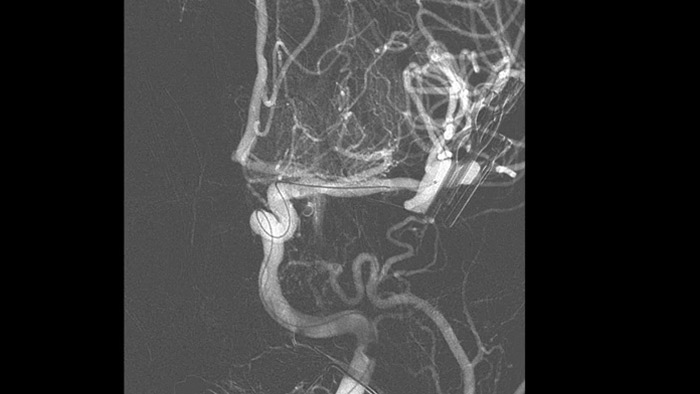

O SmartCT Angio é uma técnica de aquisição de raios X que gera uma visualização 3D completa de alta resolução do sistema vascular cerebral a partir de um único processamento de angiografia rotacional, tudo controlado através do ecrã tátil na mesa. Isto pode melhorar a visibilidade de anatomia tortuosa ou complexa que pode não ser vista numa imagem 2D ou DSA.

O SmartCT Angio proporciona uma vista volumétrica em alguns segundos1 para auxiliar na avaliação da localização, tamanho, pescoço e gravidade do aneurisma para planeamento do tratamento. Os volumes 3D são visualizados com alta resolução espacial e compensação automática do movimento do paciente.